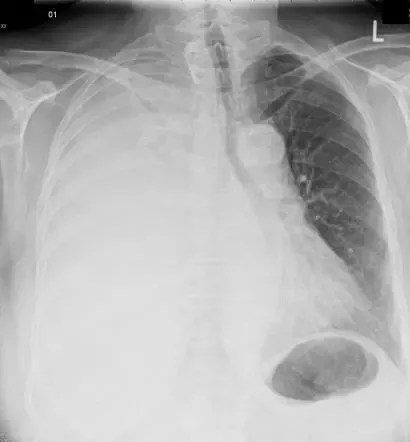

Jul 17, 2021 · what do you mean by apicolordotic view haziness. What is the meaning of apicolordotic view shows coarse reticular and hazy densities in the right lung apex? What is a high d dimer test result. What is a normal healthy fibroscan result. What is normal for hemoglobin results. 44 years experience family medicine. It does not necessarily mean you're sick. It means there is something in the uppermost part of the right lung that needs to be further evaluated, unless the diagnosis is already known. The rest of the report you have posted suggests that something (suspicious opacities) are seen in the right lung. What is bacteria flora on pap smear result. It means the radiologist sees something high up in the lung, but because it is partially obscured by the shadows of the clavicle, the anterior first rib and/or the posterior 2nd and 3rd ribs, she is not sure exactly what it is.